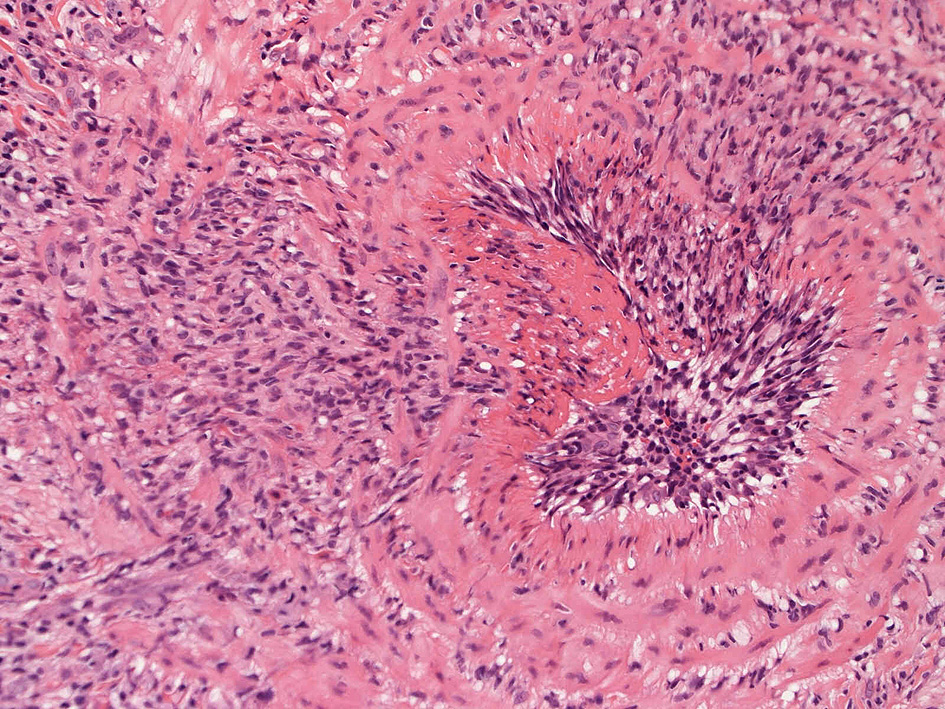

皮膚の血管(静脈・細動脈)病変、脂肪織炎 (サムネイルをクリックすると大きな画像が見られます)

Bec01.jpg

fibrinoidnecrosis01.jpg

vasculitisYa.jpg

fibrinoid necrosis

obstruction.jpg

fibrinoid necrosis(拡大)

Bec05.jpg

免疫染色:血管腔を閉塞する細胞の多くはCD68, CD163陽性細胞. CD34陽性内皮が保たれている。